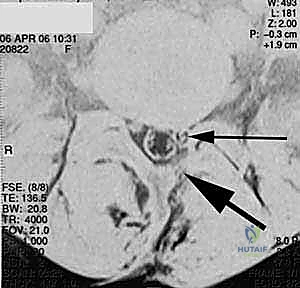

في هذه التقنية، يتم الوصول إلى العمود الفقري من الخلف مباشرة. يقوم الجراح بإزالة جزء من العظم (الصفيحة الفقرية Laminectomy) للوصول إلى القناة الشوكية. يتم سحب الأعصاب برفق إلى الجانبين للوصول إلى القرص التالف وإزالته، ثم يتم إدخال "أقفاص" (Cages) مدعومة بطعوم عظمية من كلا الجانبين.

تقنية TLIF (الاندماج الفقري القطني عبر الثقب)

تُعد TLIF تطوراً لتقنية PLIF. بدلاً من الدخول مباشرة من المنتصف وسحب الأعصاب بشكل كبير، يتم الوصول إلى القرص الغضروفي من جانب واحد عبر "الثقبة" (Foramen) - وهي الفتحة التي يخرج منها العصب.

الخطوة 2: إزالة الضغط العصبي (Decompression)

يقوم د. هطيف بإزالة الأجزاء العظمية الضاغطة (Laminectomy أو Facetectomy) والأربطة المتضخمة بدقة ميكروسكوبية لتحرير الأعصاب الشوكية المختنقة.

الخطوة 3: استئصال القرص التالف (Discectomy)

يتم تفريغ القرص الغضروفي التالف بالكامل، وإعداد المساحة بين الفقرتين (Endplates) لاستقبال الطعم العظمي. هذه الخطوة حاسمة لضمان التحام العظام لاحقاً.